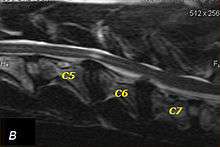

T2 weighted MRI in neutral (A) and linear traction (B) of a seven-year-old Doberman with a two-year history of cervical pain treated with NSAIDs and presented acutely tretraplegic: A C6-C7 and C5-C6 traction responsive myelopathy are evident on MRI. The spinal-cord hyperintensity seen at the C5-C6 is suggestive of chronic lesion and most likely responsible for the chronic history of cervical pain, while the C5-C6 lesion was most likely responsible for the acute tetraplegia.

Same dog (A) treated with double implant (B) three days after surgery: The dog became ambulatory three days after surgery. Four weeks after surgery, it had ataxia without conscious proprioceptive deficits, and three months after surgery, the dog was neurologically normal. The owner reported it had been two years since the dog was able to hold its neck in an elevated position.